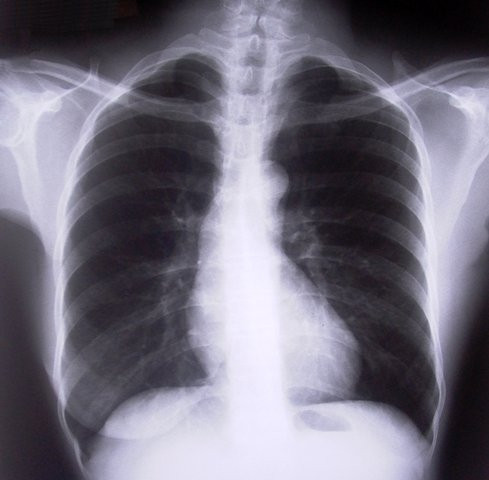

He said lack of data on COPD-related deaths was alarming. PHOTO: FILE

He said lack of data on COPD-related deaths was alarming.